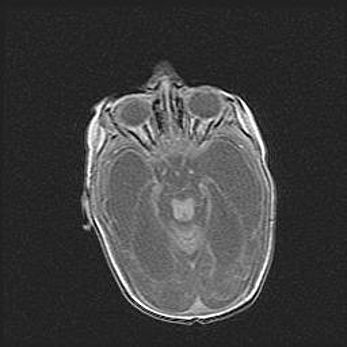

Мальформация Денди-Уокера. Киста задней черепной ямки.

Агенезия мозолистого тела.

Возраст: 2,5 месяца

Вес: 2420 г

Пол: женский

Окружность головы: 37 см

Срок гестации: 32 недели

Мальформация Денди—Уокера — редкий вид патологии ЦНС, представляющий собой врожденный порок развития каудального отдела ствола и червя мозжечка, ведущий к неполному раскрытию срединной (Мажанди) и латеральных (Лушка) апертур IV желудочка мозга. Для этогно синдрома характерна триада симптомов: гипотрофия червя мозжечка и/или полушарий мозжечка, кисты задней черепной ямки, гидроцефалия различной степени. В 70% случаев порок сочетается и с другими аномалиями головного мозга, в частности с агенезией мозолистого тела.